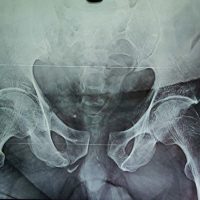

A 52-year-old male presented with right knee medial pain for 3 months, exacerbated by stair climbing and squatting, associated with popping and locking sensations. On physical examination, the range of motion (ROM) of the right knee is mildly limited by pain during flexion, medial joint line tenderness, and a positive McMurray test for the posterior horn of the medial meniscus. Gross effusion is noted, with aspiration yielding 40 cc of serous fluid containing chondral debris. Radiographs and scanography reveal no significant mechanical axis deviation, and the knee appears grossly normal on imaging. He denies any recent trauma but has a history of an old femoral fracture treated with surgical fixation and subsequent implant removal (Fig. 1).

Figure 1: Full-length frontal radiographs of both lower extremities show no significant mechanical axis deviation.